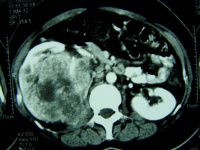

4.CT扫描:CT对肾癌的诊断有重要作用。可以发现未引起肾盂肾盏改变和无病状的肾癌,可准确的测

定肿瘤密度,并可在门诊进行CT可准确分期。有人统计其诊断准确性:侵犯肾静脉91%,肾周围扩散78%,淋巴结转移87%,附近脏器受累96%。肾癌CT检查表现为肾实质内肿块亦可突出于肾实质肿块为圆形,类圆形或分叶状边界清楚或模糊,平扫时为密度不均匀的软组织块,CT值>20Hu,常在30~50Hu间,略高于正常肾实质,也可相近或略低,其内部不均匀系出血坏死或钙化所致,有时可表现为囊性CT值,但囊壁有软组织结节经静脉注入造影剂后正常肾实质CT值达120Hu左右,肿瘤CT值亦有增高,但明显低于正常肾实质,使肿瘤境界更为清晰,如肿块CT值在增强后无改变可能为囊肿结合造影剂注入前后的CT值为液体密度即可确定诊断肾癌内坏死灶肾囊腺癌以及肾动脉栓塞后注入造影剂以后CT值并不增高肾血管平滑肌脂肪瘤由于其内含大量脂肪CT值常为负值内部不均匀增强后CT值升高但仍表现为脂肪密度嗜酸细胞瘤在CT检查时边缘清晰内部密度均匀一致增强后CT值明显升高。